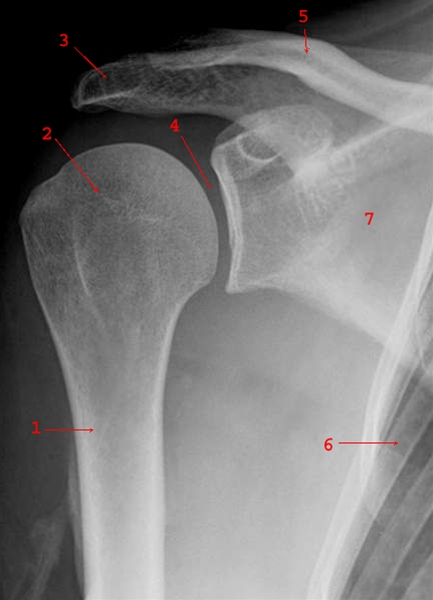

Skulder, røntgen, normal forfra

Figur 1

Normalt forfra billede af højre skulder (AP-projektion)

- Humerus (overarmsknoglen)

- Caput humeri (ledhovedet øverst på overarmsknoglen)

- Acromion (Skulderhøjden)

- Ledspalte

- Clavicula (kraveben)

- Costa (ribben)

- Scapula (skulderblad)